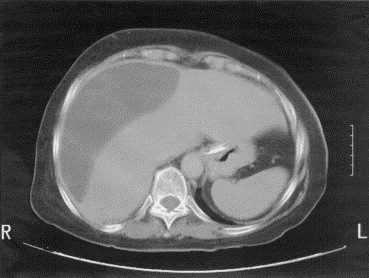

No es raro que los pacientes tengan múltiples bilomas. Los bilomas extrahepáticos se forman predominantemente en el cuadrante superior derecho del abdomen. Sin embargo, en alrededor del 40% de los casos, la bilis migra sobre la parte anterior del hígado hacia los espacios subfrénico o subhepático izquierdo.